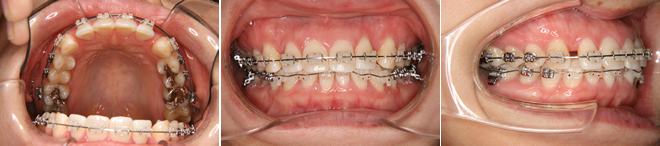

| 主訴 | 前歯の隙間が気になる |

| 年齢・性別 | 42歳 / 女性 |

| 治療方針 | 咬合力により上顎前歯が前方に傾斜したと思われるケース。元に戻りやすいため過蓋咬合をしっかり治して、保定には固定式のリテーナーも併用する。 |

| 抜歯部位 | 非抜歯 |

| 使用装置 | マルチブラケット装置 |

| 治療期間 | 16か月 |

| リテーナー | 上顎インビジブル、フィックス、下顎インビジブル |

| 費用 | 765,000円(税別) |